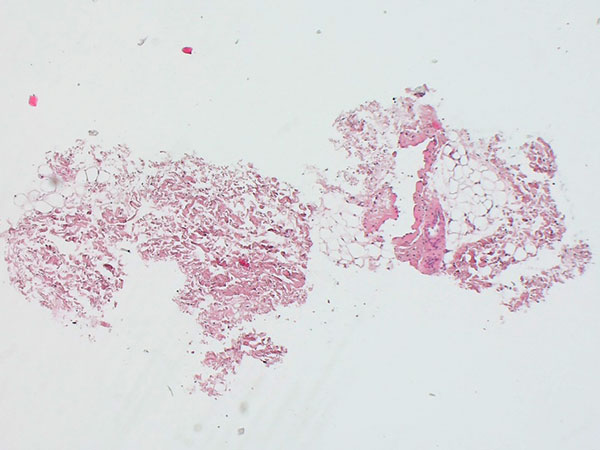

Histopathological image, hematoxylin & eosin stain (HE), here 25-fold overview magnification: A dysplastic, vein-like irregular vascular cavity is found. This is embedded in normal adipose tissue and stroma.

Histopathological workup then revealed the typical findings of a benign vascular lesion with dysplastic, asymmetric irregular venous wall structure. The smooth muscular vessel wall is not formed throughout and is entirely missing in places. Histopathologically, another slow-flow vascular malformation, namely a lymphatic malformation, might be considered as a differential diagnosis. This could easily be differentiated with podoplanin stain (D2-40) to distinguish between venous malformation (D2-40-negative endothelia) and lymphatic malformation (D2-40-positive endothelia). Clinically, venous malformation was clearly more likely in this case because of the blue coloration of the lesion.